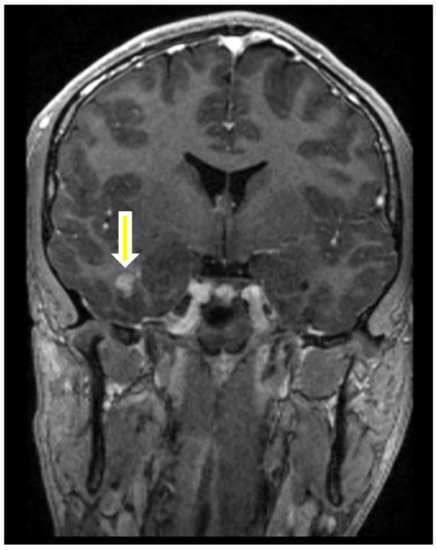

2. Case Presentation